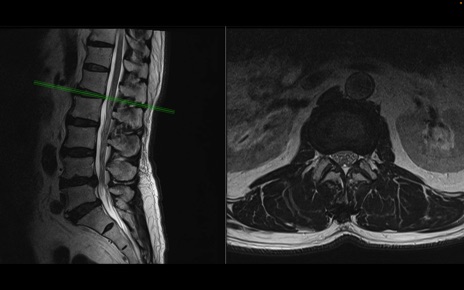

【整形】TIPS症例2 腰椎MRI 横断像と矢状断像

【症例】70歳代男性

【主訴】左下肢痛

【現病歴】2週間前くらいから腰痛、左下肢痛あり。左臀部から大腿、下腿外側のしびれが常時ある。歩行とともに同部位の痛みあり。

【身体所見】Lasegue70-/60+、Bragard-/±、PTR ±/±、ATR -/-、IP 5/5、TA 5/4、TS 5/5、EHL 右第1足趾なし/3、FHL 5/5、hypersthesia(-)、足背動脈触知良好

異常所見と診断は?